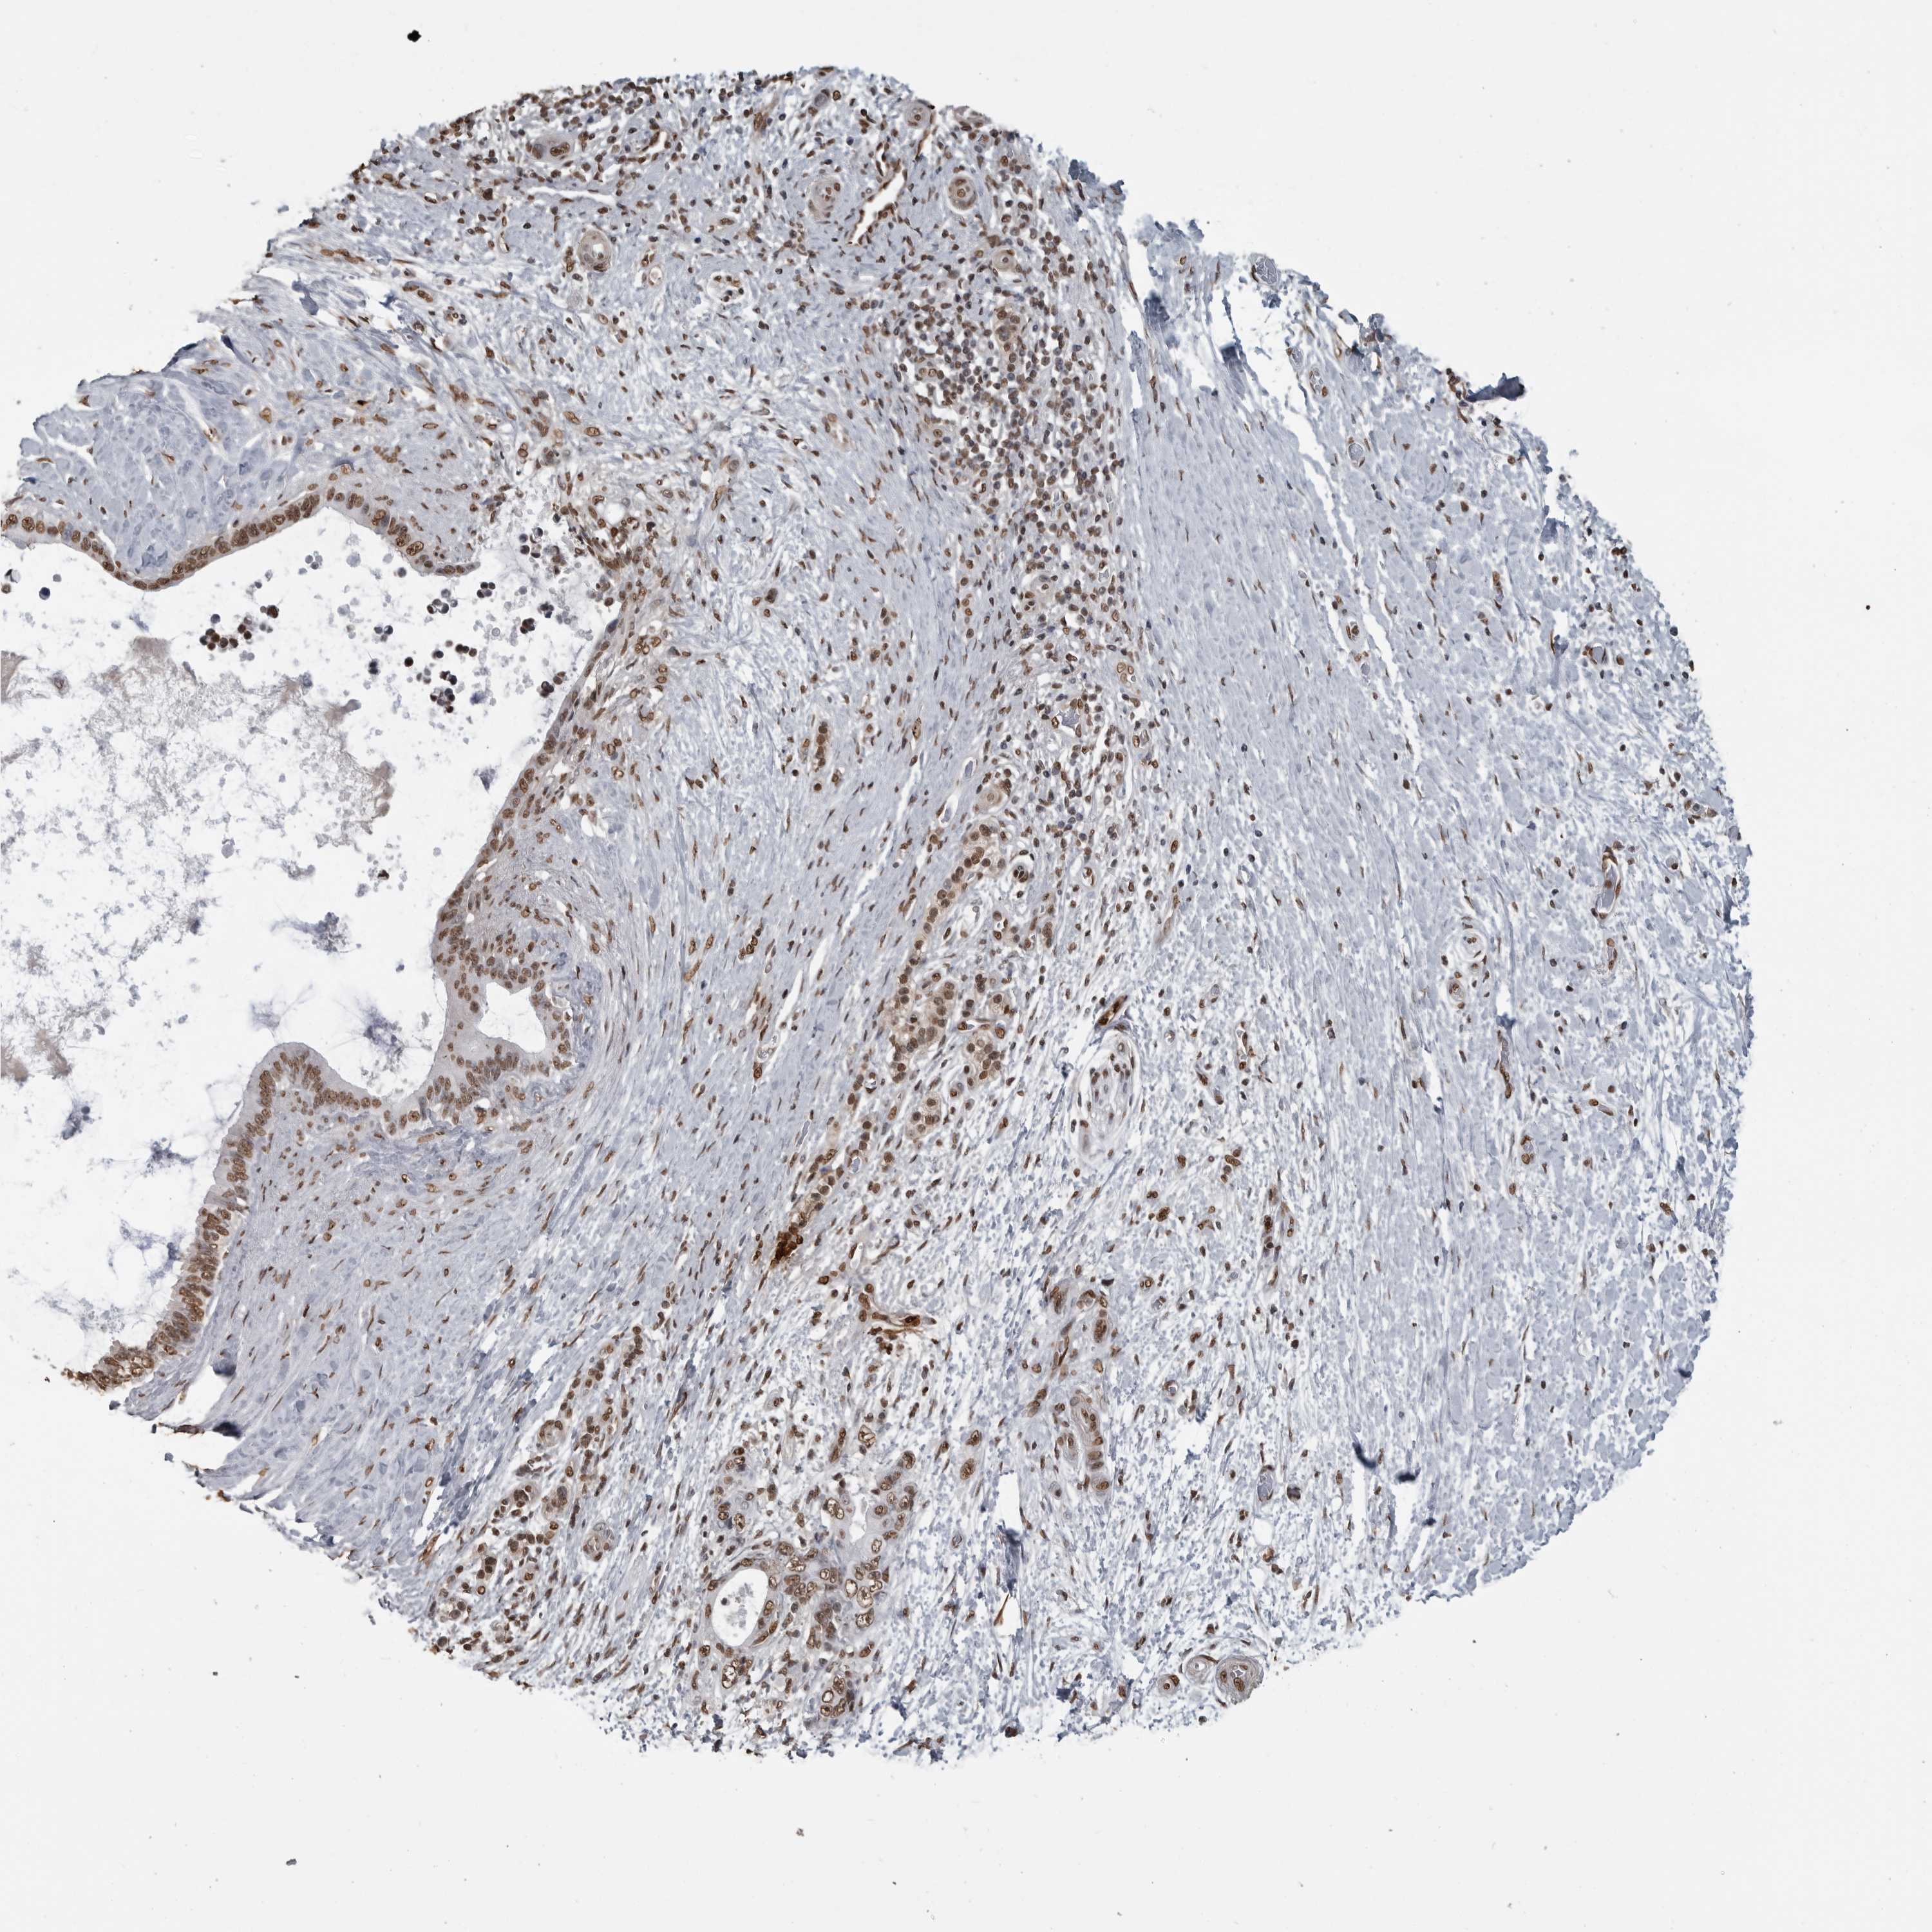

PANCREATIC CANCER - Protein expressioni

A mouse-over function shows sample information and annotation data. Click on an image to view it in a full screen mode. Samples can be filtered based on level of antibody staining by selecting one or several of the following categories: high, medium, low and not detected. The assay and annotation is described here.

Note that samples used for immunohistochemistry by the Human Protein Atlas do not correspond to samples in the TCGA dataset.

Antibody stainingi

Antibody staining in the annotated cell types in the current human tissue is reported as not detected, low, medium, or high, based on conventional immunohistochemistry profiling in selected tissues. This score is based on the combination of the staining intensity and fraction of stained cells.

Each image is clickable and will lead to virtual microscopy that enables deeper exploration of all samples and also displays staining intensity scores, fraction scores and subcellular localization as well as patient and tissue information for each sample.

Antibody HPA067203

Antibody CAB025507

Antibody CAB073546

Staining

High

Medium

Low

Not detected

Intensity

Strong

Moderate

Weak

Negative

Quantity

>75%

75%-25%

<25%

None

Location

Nuclear

Cytoplasmic/membranous

Cytoplasmic/membranous,nuclear

Adenocarcinoma, NOS